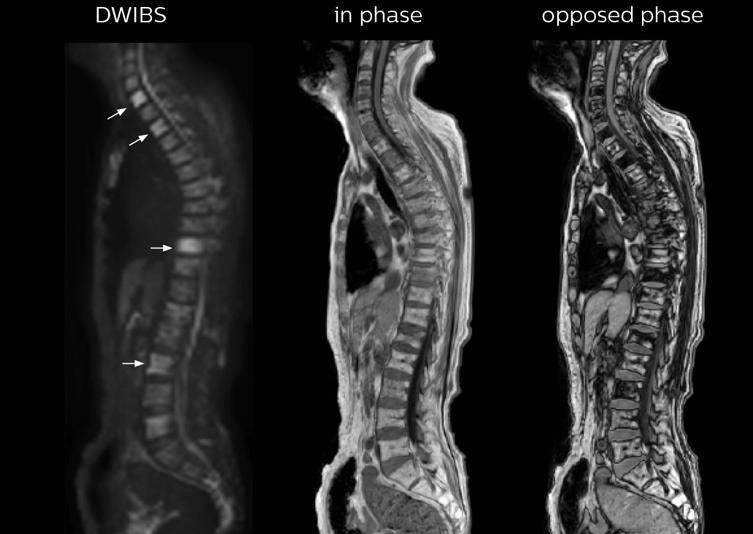

“In-phase and out-phase sagittal T1-weighted FFE images help us to visualize and further characterize bone lesions such as metastasis and bone-marrow hyperplasia that have high signal on DWI. These images are also used throughout radiotherapy, to monitor changes in the fatty bone marrow.”

Mr. Naka remembers some cases where DWIBS provided remarkable information. “In one example, DWIBS visualized bone lesions that could not be seen on PET or SPECT. In another case we had found a bone lesion when a normal L-spine scan for narrowing of the disk space was done. One extra DWIBS scan (2 stations, 8 minutes) demonstrated a lesion that later was confirmed to be the primary region of cancer.”